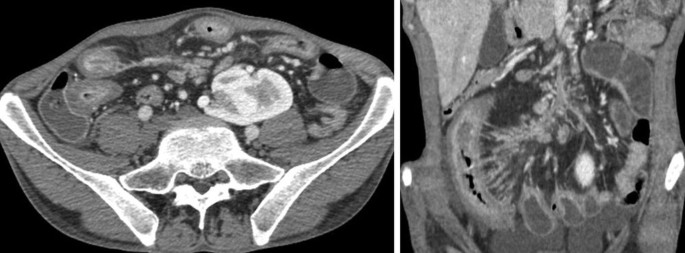

Abdominal Ct Scan Showing Interstitial Edema Of The Pancreas With The Download Scientific Diagram